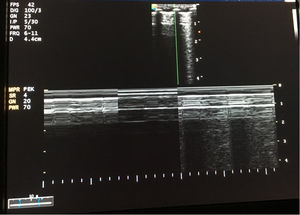

Paciente de 4 meses de edad, exprematuro de 24 semanas de gestación y con displasia broncopulmonar grave, conectado a ventilación mecánica (modalidad presión control con PIP 25cmH2O, PEEP 5,5cmH2O, FR 35rpm y FiO2 30%). El día que describimos, el paciente precisaba FiO2 de hasta el 50% y en la radiografía de tórax (fig. 1) mostraba hiperinsuflación intensa del hemitórax derecho y ausencia de deslizamiento pulmonar en la ecografía pulmonar (fig. 2). Dada la evolución de los pacientes con displasia broncopulmonar hacia la compresión dinámica de la vía aérea distal, se decidió incrementar progresivamente PEEP, sin mejoría ecográfica hasta llegar a una PEEP de 10cmH2O, donde se evidenció reaparición del deslizamiento pleural (fig. 3), y en la radiografía de tórax resolución parcial de la sobredistensión (fig. 4).